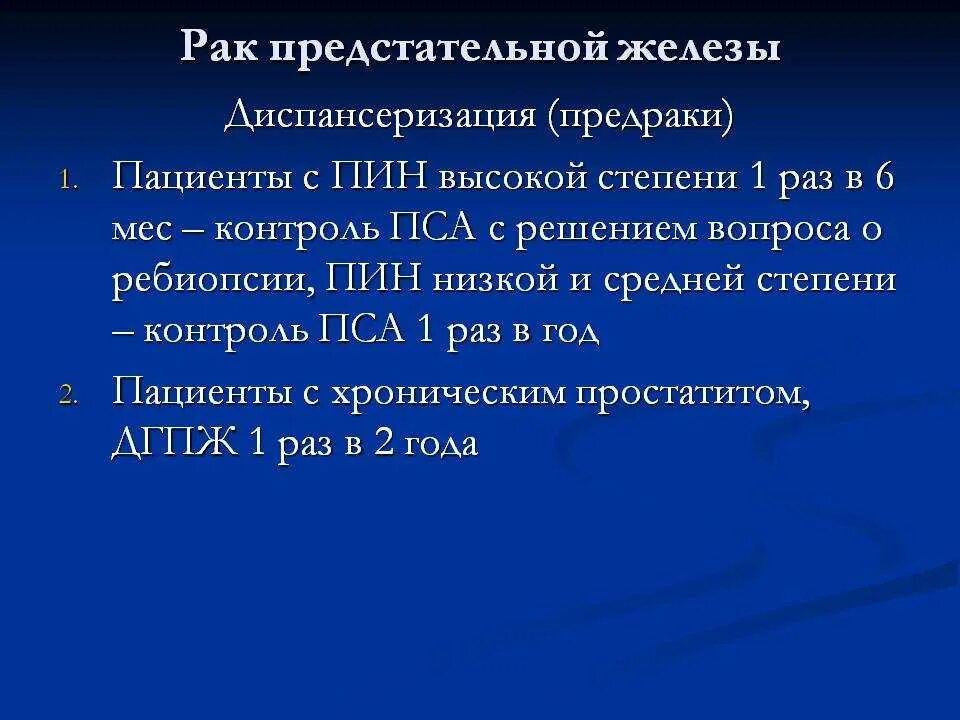

Злокачественное Перерождение предстательной железы Гистологическая классификация опухолей предстательной железы. Простатическая интраэпителиальная неоплазия. Опухоли предстательной железы факторы. Предраковые заболевания предстательной железы

Гистологическая классификация опухолей предстательной железы. Простатическая интраэпителиальная неоплазия. Опухоли предстательной железы факторы. Предраковые заболевания предстательной железы Злокачественное новообразование предстательной железы. Метастазы предстательной железы. Карцинома предстательной железы. Злокачественные новообразования простаты

Опухоли предстательной железы классификация. Злокачественное новообразование предстательной железы. Опухоль предстательной железы т2. Стадии ЗНО предстательной железы Опухоль предстательной железы пса. Что такое РПЖ предстательной железы. Степени опухолей простаты. Предрак предстательной железы

Опухоль предстательной железы пса. Что такое РПЖ предстательной железы. Степени опухолей простаты. Предрак предстательной железы Склероз предстательной железы. Атрофия предстательной железы. Гистологический атлас биопсий предстательной железы